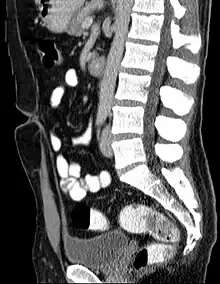

Coupe scanographique sagittale montrant l'ouraque sur toute sa hauteur. Ce cordon fibreux s'étend en avant et en haut de la vessie sur la ligne médiane jusqu'au nombril.